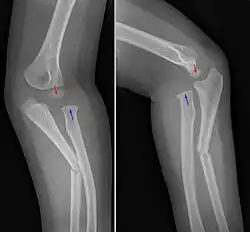

Monteggiova zlomenina je zlomenina proximální třetiny ulny (kosti loketní) v kombinaci s luxací (vykloubením) hlavice radia (kosti vřetenní). Nejčastěji vzniká přímým nárazem na zadní stranu předloktí nebo pádem na ruku flektovanou (ohnutou) v lokti.